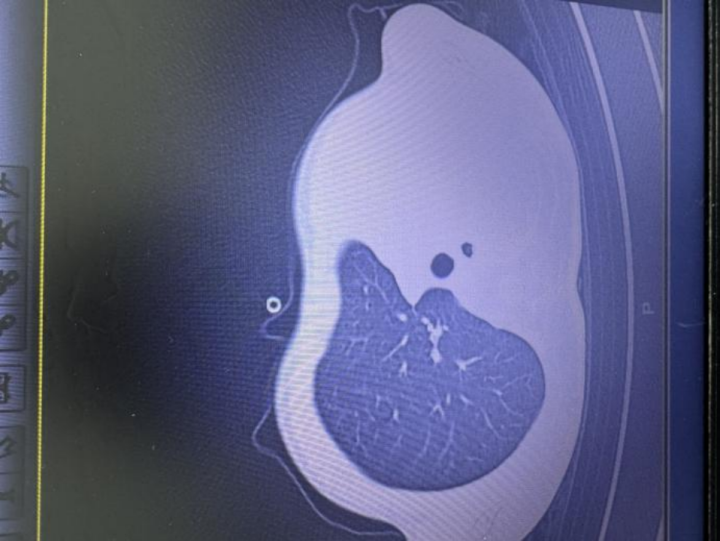

因流感进ICU,肺里堵满"痰栓" 引发网友关注 11岁男孩 本文转自【央视网】; "早上开始发烧,晚上肺就白了" 近日,浙江11岁男孩 早上发烧,晚上就"白肺" "一天时间,这个孩子从轻微发烧咳嗽,直接发展到肺堵死、喘不上气,去鬼门关走了一遭!"浙江大学医学院附属儿童医院杨子浩主任医师披露了这个男 孩的遭遇。 2025年12月1日早上,11岁男孩小宇(化名)开始发烧,最高到38.9℃,伴有轻微咳嗽和喘息。家人以为是感冒,给孩子服用头孢、易坦静、柴胡等药, 却没想到病情会在一天内急转直下。 到12月1日晚上,小宇咳嗽加剧,喘得越来越急,还喊胸口疼,没法躺平。 12月2日早上,孩子呼吸急促、嘴唇发紫、精神不振,家人急忙将他送到浙江大学医学院附属儿童医院急诊。这时,距小宇出现发热,刚好差不多一天。 急诊检查结果让医护人员瞬间紧张:验血显示炎症指标大幅上升,胸片发现左侧肺叶几乎不工作了,影像学中变成大片白色,即通常所说的"白肺",意味 着肺功能严重受损,孩子已经缺氧,随时有窒息危险。 图:影像显示肺白了一半 "这是流感合并细菌感染引起的严重肺炎,同时发生了坏死性喉气管支气管炎,并有严重并发症,若不及时处理,几小时就可 ...